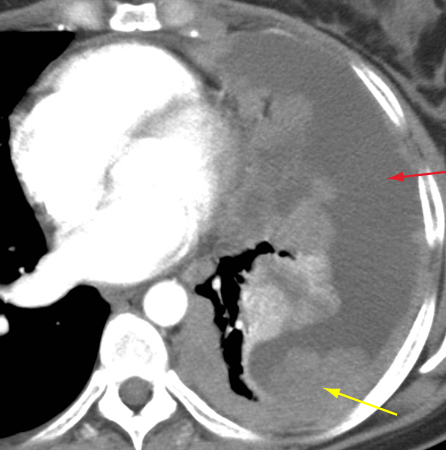

[Figure caption and citation for the preceding image starts]: Tomografia computadorizada (TC) do tórax mostrando timoma em estádio IVA de Masaoka-Koga com derrame pleural (seta vermelha) e vastas metástases pleurais (seta amarela) juntamente à parede torácica posteriorDo acervo de Cameron Wright, MD; usado com permissão [Citation ends].

O hemograma completo, embora inespecífico, pode apresentar anemia decorrente de aplasia paraneoplásica pura de células da série vermelha. Título elevado de anticorpos contra o receptor da acetilcolina (a faixa varia com o teste utilizado) está presente em 80% a 90% dos pacientes com miastenia gravis e pode auxiliar no diagnóstico.[31] Aproximadamente 5% a 10% dos pacientes com timoma na ausência de miastenia gravis podem apresentar elevação do anticorpo sérico contra o músculo estriado.[32] Isso pode ser útil em situações difíceis de diagnóstico.[Figure caption and citation for the preceding image starts]: Tomografia computadorizada (TC) do tórax mostrando timoma em estádio IVA de Masaoka-Koga com derrame pleural (seta vermelha) e vastas metástases pleurais (seta amarela) juntamente à parede torácica posteriorDo acervo de Cameron Wright, MD; usado com permissão [Citation ends].